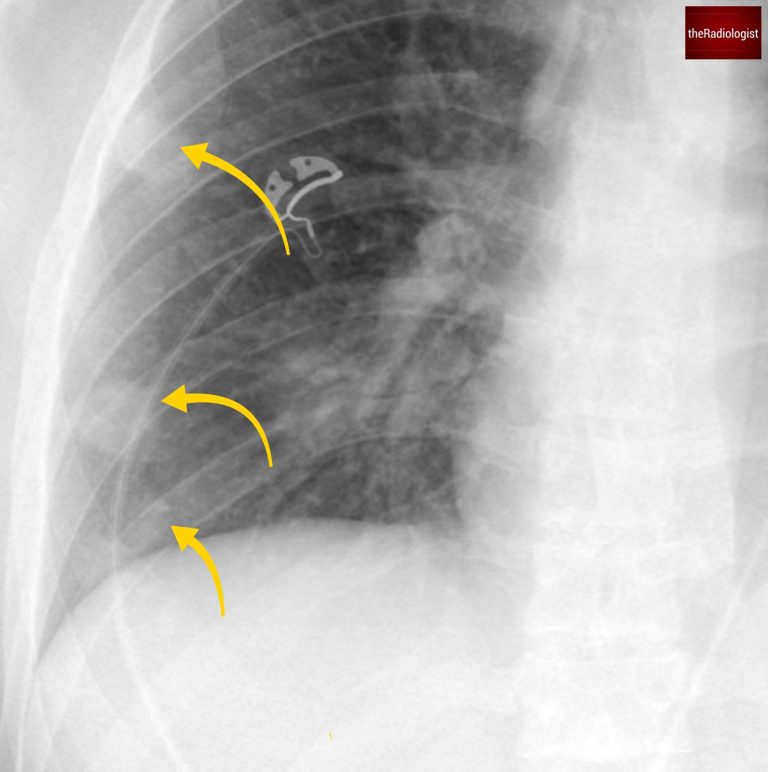

The chest X-ray shows several nodules in the right lung, predominantly in the middle and lower zones.

Note that these nodules are notably peripheral, with no evidence of pleural effusion.

There are several peripheral nodules within the right lung (yellow arrow). There are further nodules seen centrally overlying the hilar vessels in addtion.